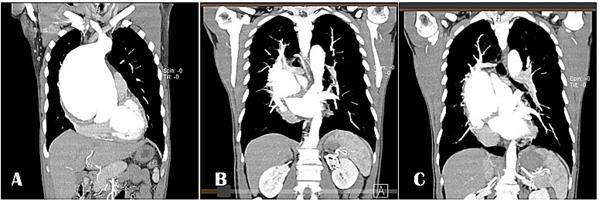

Tomografía computarizada (TC) de tórax. Realizado cuatro horas posterior al ingreso del paciente (Imagen 1 y 2).

IMAGEN 1 . TC. Aneurisma voluminoso de la raíz aórtica que compromete la aorta ascendente que mide 14 x 13 cm, (Imagen A) Flap de disección que separa la luz verdadera de la falsa, dicho flap compromete la raíz aórtica, la aorta ascendente y se extiende hasta el extremo proximal de la aorta descendente (Imagen A y B).

IMAGEN 2. Reconstrucción tridimensional de aortografia por TC: Observe

flechas Aneurisma sacular

disecante de aorta

ascendente con extensión al cayado y parte de aorta descendente (Tipo A de Stanford). Imagen A reconstrucción imagen lateral, Imagen B reconstrucción imagen frontal.